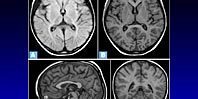

Она провоцирует целый набор тяжелых нарушений в работе нейронов, связанных со сбоями в функционировании лизосом (отвечают за внутриклеточное переваривание и секрецию). Так как лизосомы не работают должным образом, происходит накопление липофусцина в нейронах. Данное вещество известно также как «пигмент старения», встречающийся во всех тканях и органах человека. Итог накопления — массовая гибель нервных клеток и постепенная атрофия мозга.

По словам генетиков, MFSD8 отвечает за перенос белков и других молекул внутри лизосом, и его повреждение тоже выводит их из строя. Эксперты подчеркивают: многие тяжелые болезни мозга, вызванные генетическими мутациями, похожи друг на друга. Из-за этого трудно поставить диагноз, а лечение во многих случаях просто невозможно. Специалисты советуют: будущие родители должны проходить тесты на наличие подобных мутаций в их геноме еще до первых попыток зачать.